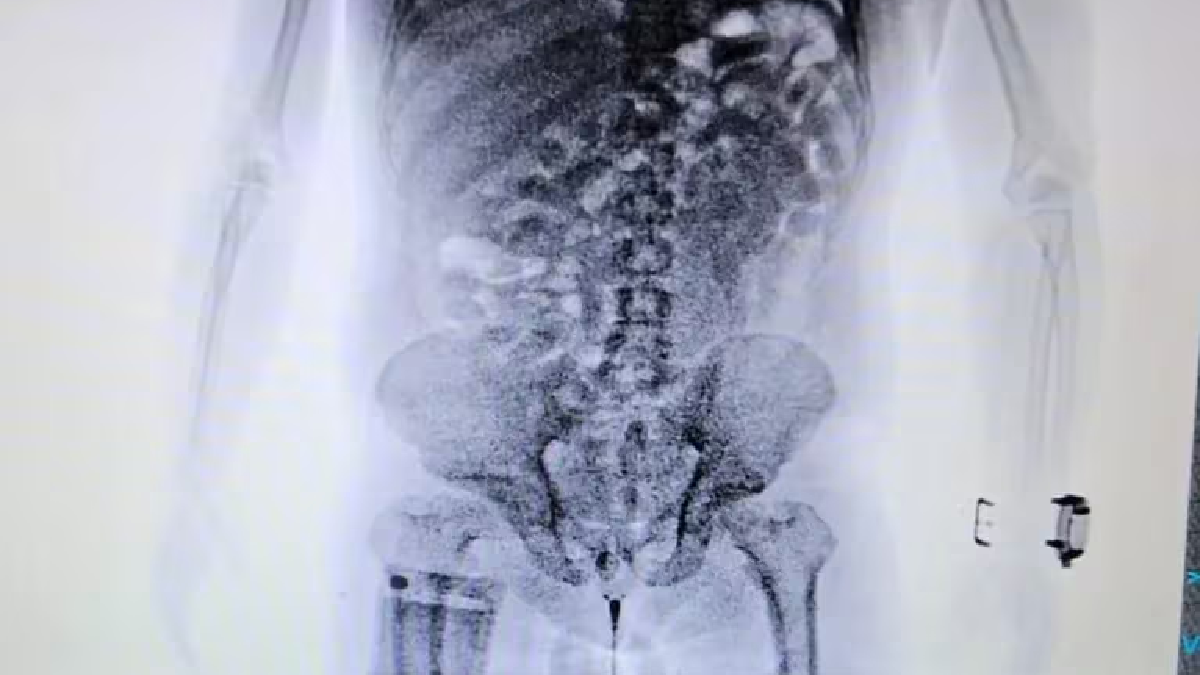

El episodio ocurrió en el Aeropuerto Internacional de Ezeiza. Los agentes de la Aduana descubrieron que un ciudadano brasileño llevaba 84 cápsulas de cocaína en su organismo instantes previos a abordar un vuelo de Air France con destino a Málaga, España.